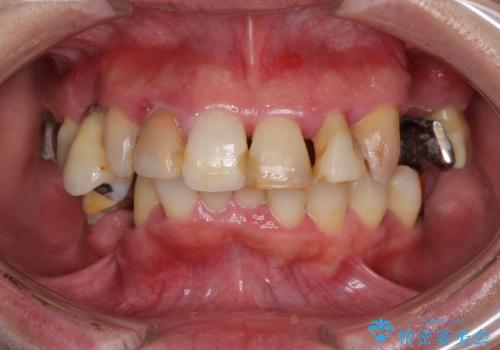

- 銀歯が外れてしまったとのことで来院された患者様です。

上顎奥の粘膜に近い部分で、外れた銀歯の下には大きく虫歯が広がっていました。

虫歯をしっかりと取り除き、ゴールドインレーにて修復することとしました。

ゴールドインレーは銀歯のインレーやセラミックインレーと比べ、「技工操作の精度が高く、適合が著しく良い」というメリットがあります。特に上の奥歯は歯科医師の操作が行いにくいため、「適合の良さ」は再治療のリスクを防ぐ上でとても重要な要素となります。

上の奥歯は金属色が見えることもないため、審美的な問題は全くありません。

咬み心地はとても良好で、全く違和感がなく、患者様には大変満足していただきました。